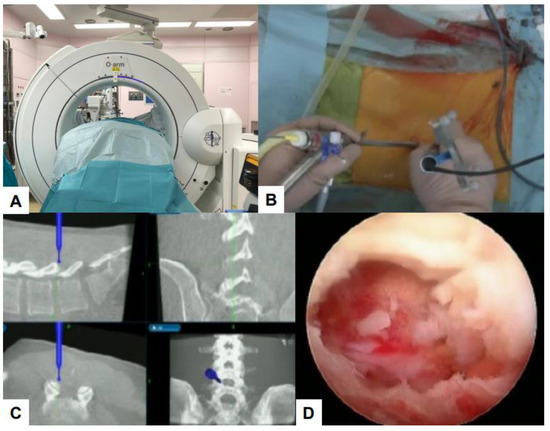

- Zygogiannis, K.; Tanaka, M.; Sake, N.; Arataki, S.; Fujiwara, Y.; Taoka, T.; Uotani, K.; Askar, A.E.K.A.; Chatzikomninos, I. Our C-Arm-Free Minimally Invasive Technique for Spinal Surgery: The Thoracolumbar and Lumbar Spine-Based on Our Experiences. Medicina 2023, 59, 2116. [Google Scholar] [CrossRef] [PubMed]

- Tanaka, M.; Sonawane, S.; Uotani, K.; Fujiwara, Y.; Sessumpun, K.; Yamauchi, T.; Sugihara, S. Percutaneous C-Arm Free O-Arm Navigated Biopsy for Spinal Pathologies: A Technical Note. Diagnostics 2021, 11, 636. [Google Scholar] [CrossRef]